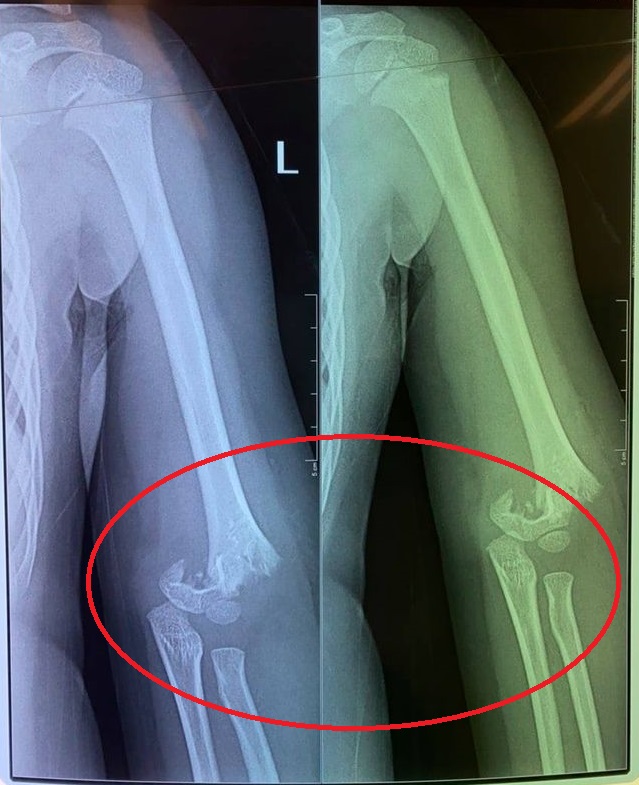

Con chị H. đã bị 1 bạn cùng lớp đẩy ngã từ cầu trượt văng ra ngoài làm gãy khuỷu tay. Tuy nhiên nhà trường lại không đưa bé T. đi bệnh viện luôn. Con chị sau đó phải làm phẫu thuật ở bệnh viện Xanh Pôn.

Con chị H. bị bạn đẩy ngã gãy tay.

"Điều quan trọng là con bị ngã gẫy tay từ sáng mà đến 12h trưa giáo viên mới cho con đi bệnh viện. Lúc con ngã, cô không đưa đi khám luôn mà lại đưa con vào lớp, để các bạn ăn uống xong xuôi rồi mới gọi một chiếc xe tư nhân đưa con đi mà không phải xe cấp cứu. Nếu là xe cấp cứu thì họ còn có thể sơ cứu, nẹp tay cho con", chị H. bức xúc cho biết.